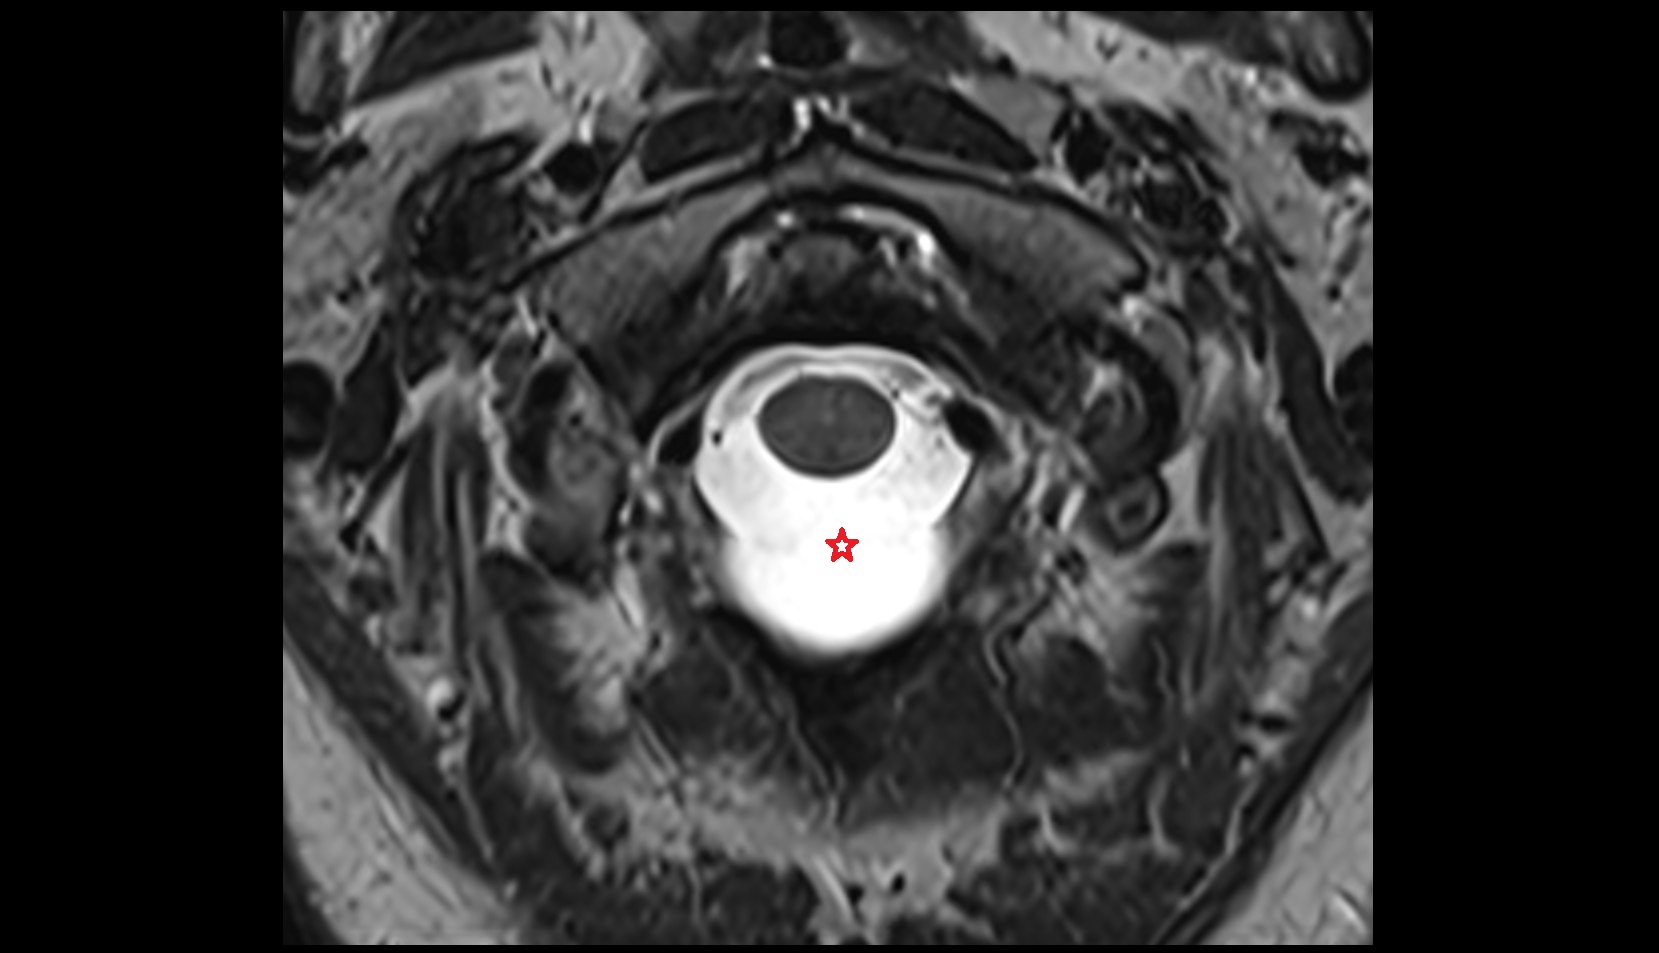

- Spinal cord

- Nucleus pulposus of intervertebral disc

- subarachnoid space of spinal cord